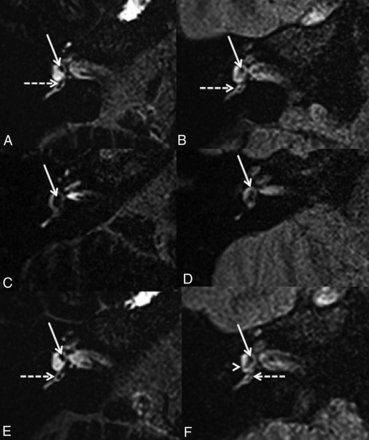

With hVFA sequences (Fig 2), cochlear BLB impairment was observed in 6/32 ears (18.7%) (6/19 symptomatic and 0/13 asymptomatic ears) according to reader A and 4/32 ears (12.5%) according to reader B (4/19 symptomatic, 0/13 asymptomatic ears). The Cohen κ coefficient was 0.53. There was no significant association between cochlear BLB impairment and clinical symptomatology (P = .06 for reader A and P = .12 for reader B).

A 63-year-old woman with right definite MD. A, Axial CFA at the level of the basal turn of the cochlea shows a marked right cochlear BLB impairment compared with the left side (white arrow). B, The right cochlear BLB impairment (white dotted arrow) is less obvious with hVFA.

With CFA sequences (Fig 2), cochlear BLB impairment was observed in 8/32 ears (25.0%) according to both readers (8/19 symptomatic and 0/13 asymptomatic ears). Interreader agreement was perfect (Cohen κ coefficient = 1). There was a significant association between cochlear BLB impairment and clinical symptomatology (P = .01).